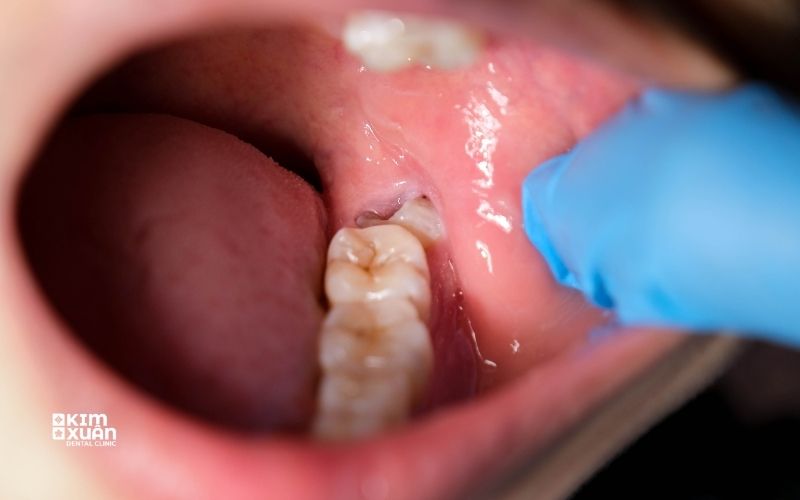

2.2. Nướu sưng đỏ, căng cứng

Phần nướu tại vị trí răng khôn có thể sưng, đỏ và đau khi chạm vào. Tình trạng này có thể giảm rồi tái phát nhiều lần.

3. Răng Khôn Mọc Ngầm Có Nguy Hiểm Không?

Câu trả lời là có thể nguy hiểm nếu không được theo dõi và xử lý kịp thời. Trên thực tế, răng khôn mọc ngầm có thể gây ra nhiều biến chứng như:

Viêm nướu tái phát nhiều lần

Sâu răng hoặc tổn thương răng số 7 kế cận

Tiêu xương hàm quanh răng khôn

Hình thành nang quanh thân răng

Chính vì vậy, ngay cả khi chưa xuất hiện đau nhức rõ rệt, răng khôn mọc ngầm vẫn cần được kiểm tra định kỳ để phát hiện sớm và phòng ngừa biến chứng.